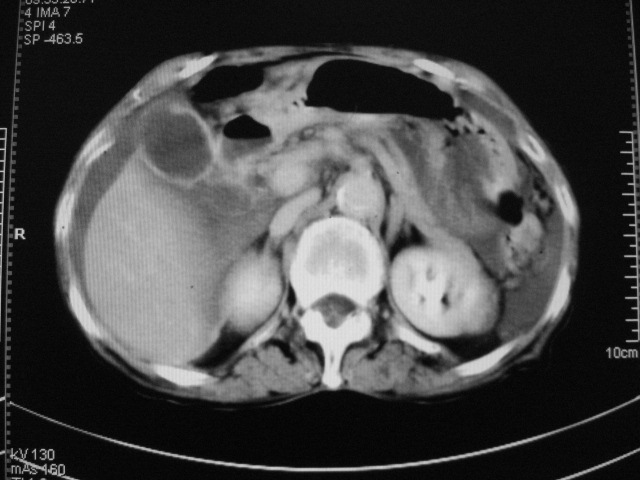

以下是引用zjzjr在2007-9-20 19:15:00的发言:[br]慢性胆囊炎伴炎性息肉可能性大.腹水.

以下是引用默契在2007-9-20 17:29:00的发言:[br][br] [br] 考虑:1、胆囊占位性病变(以癌可能性大);[br] 2、中量腹水。 [br] [br]

以下是引用快乐男生在2007-9-20 15:32:00的发言:[br]图像质量不好:[br]胆囊增大,囊壁增厚,[br]可见结节突出囊腔内,[br]增强后与囊壁相仿.[br]考虑多为胆囊慢性炎症伴有胆囊体部的息肉